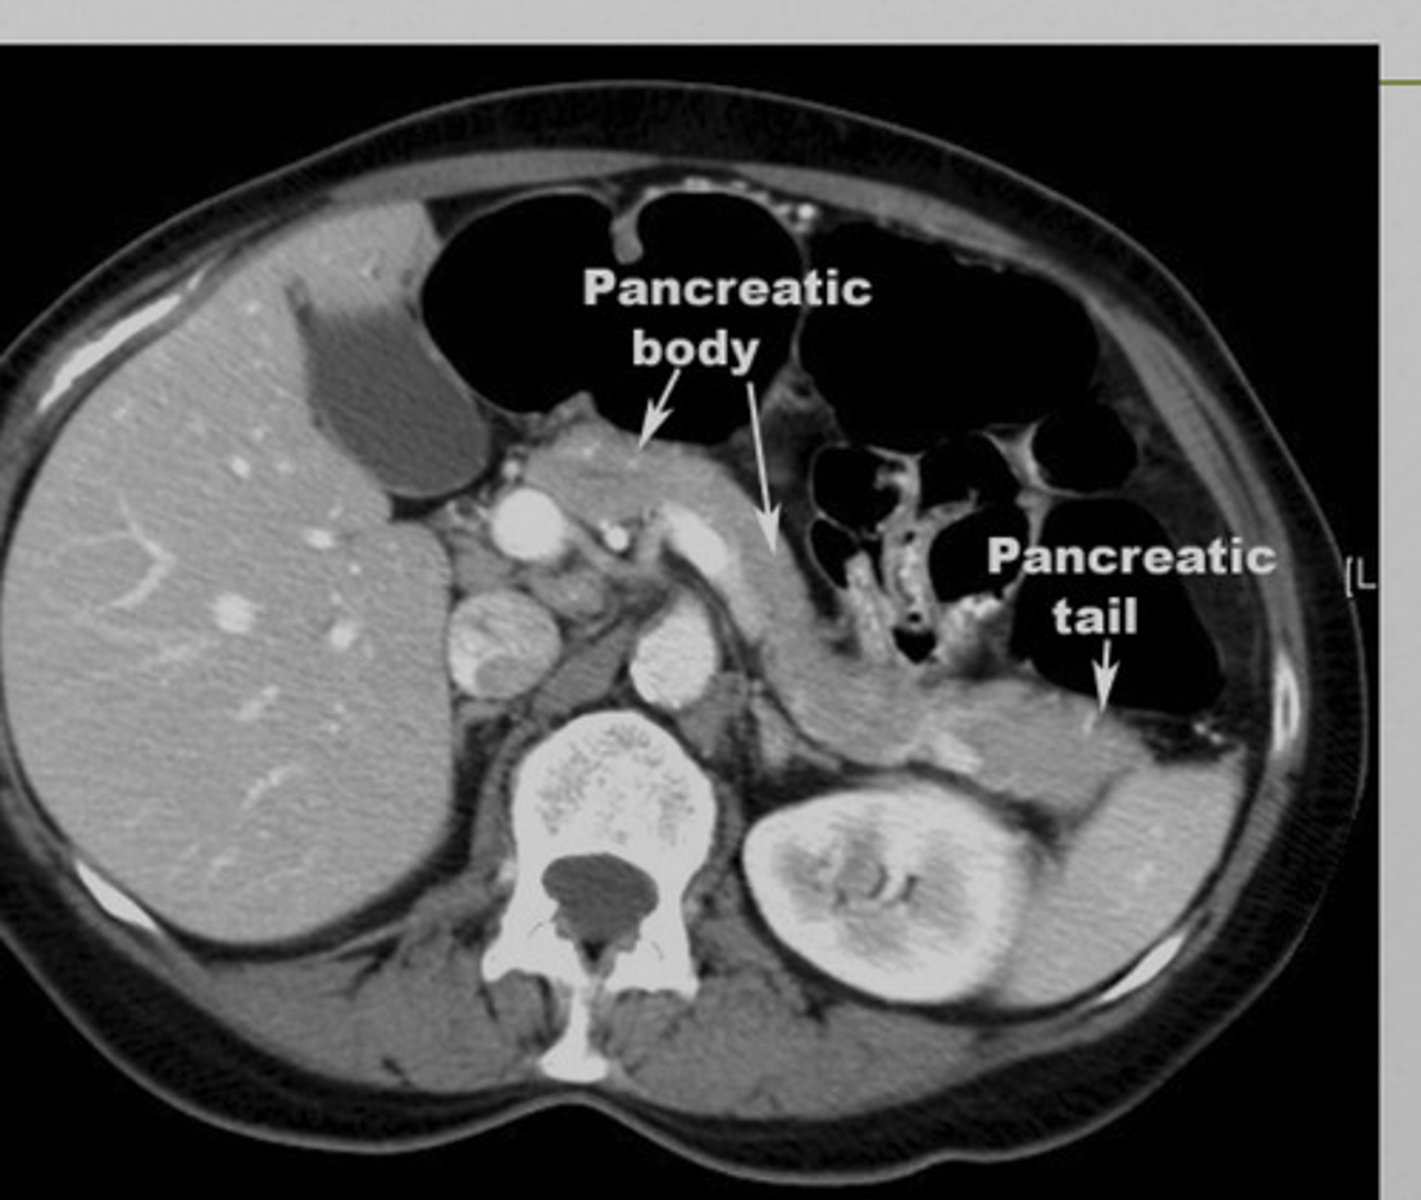

pancreas imaging

xray- may show calcified gallstones, localized ileus

US- not helpful in acute pancreatitis, may identify gallstones

CT- differentiating pancreatitis from other possibilities, enlarged pancreas

pancreatitis imaging

may appear enlarged and irregular, infiltration of peripancreatic fat, fluid surrounding